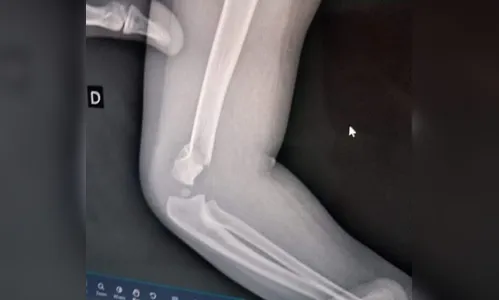

Bebê volta para casa com braço quebrado e família acusa professora

A criança passou por uma cirurgia de emergência e segue internada

Uma família de Pinhais, na Região Metropolitana de Curitiba, fez um boletim de ocorrência na quarta-feira (21) alegando agressão contra uma criança de um ano e meio no Centro Municipal de Educação Infantil Enedina Alves Marques.

Segundo com familiares, a agressão teria ocorrido na última terça (20), por volta das 15h30, mas a família só foi avisada às 17h15. Na agenda, de acordo com o boletim de ocorrência, estava escrito que ele estava machucado desde a hora do lanche, quando o bebê teria sofrido uma fratura no braço durante uma troca de fralda.

Em nota, a Secretaria Municipal de Educação de Pinhais afirmou que assim que soube do caso instaurou processo administrativo disciplinar e determinou afastamento cautelar da servidora durante a apuração da ocorrência. A secretaria afirmou ainda que “a criança foi rapidamente encaminhada ao atendimento de emergência e que a Administração está dando o suporte necessário à família”.

A criança passou por uma cirurgia de emergência no Hospital Evangélico Mackenzie na quarta (22), onde segue internada.

A polícia já investiga o caso.